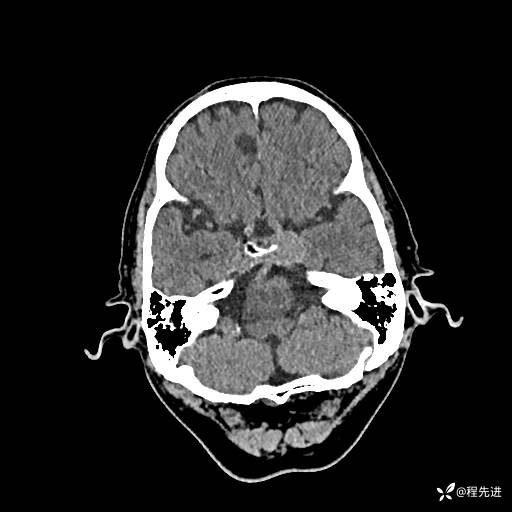

CT平扫: